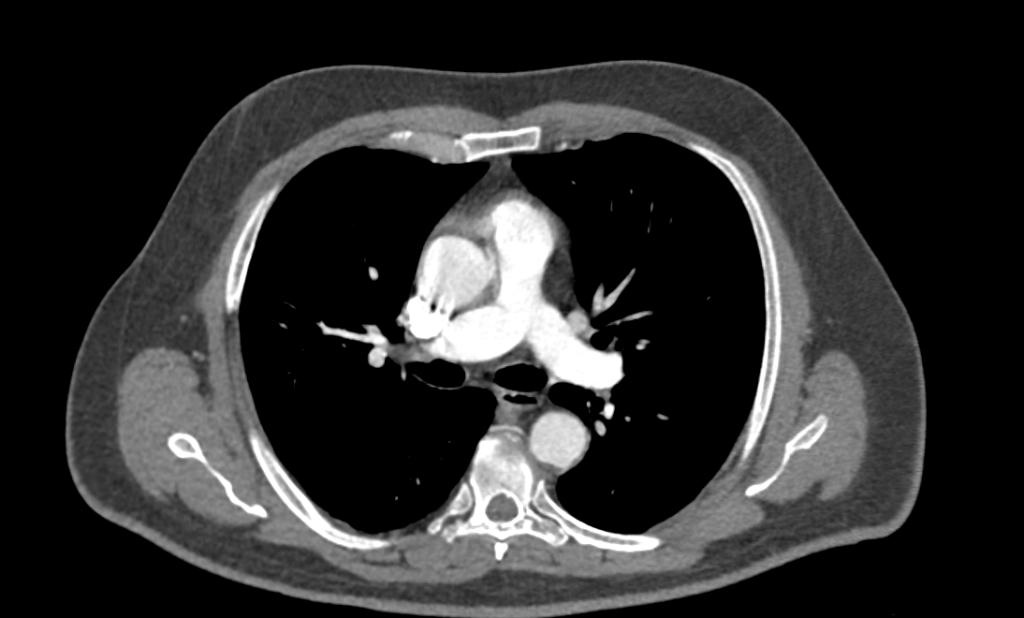

Данный препарат не токсичен, хорошо выводится организмом пациента в течении суток и не оказывает никакого пагубного воздействия на организм. Контраст может вводиться разными путями (перорально и внутривенно), но внутривенный путь введения наиболее предпочтительный. Контрастное вещество вводится преимущественно в момент проведения исследования с помощью специального медицинского изделия. За счет своих физико-химических свойств, взаимодействуя с рентгеновскими лучами, контраст задерживает их позволяя более точно визуализировать мельчайшие патологии, а также патологии сосудистого русла. После введения контрастный препарат стремительно продвигается по кровеносному руслу, тем самым попадая во все органы и ткани. В зависимости от объекта исследования, выделяют также разный фазы при которых необходимо производить фиксацию изображения. Эффект повышенной степени визуализации реализуется за счет улавливания дефектов накопления (повышения или снижения), например в злокачественных новообразованиях васкуляризация (приток крови) значительно повышена, как следствие контраст сильнее там визуализируется и имеет свойств на некоторое время (секунды) задерживается.

Применение контрастного агента зачастую необходимо в случае проведения первичной дифференциальной диагностики новообразований и уточнения детальной локализации, мониторинге результатов терапевтических/хирургических лечений онкологических заболеваний, а также для оценки сосудистого русла и его физических характеристик. Стоит отметить, что в диагностике сосудистых патологий, таких как мальформации, стенозы и атеросклеротические бляшки данный метод диагностики является “золотым стандартом””.

- Сосудистая система (мальформации, стенозы, повреждения сосудов, атеросклеротические бляшки и кальцификаты). Ранняя диагностика факторов риска развития инсульта;